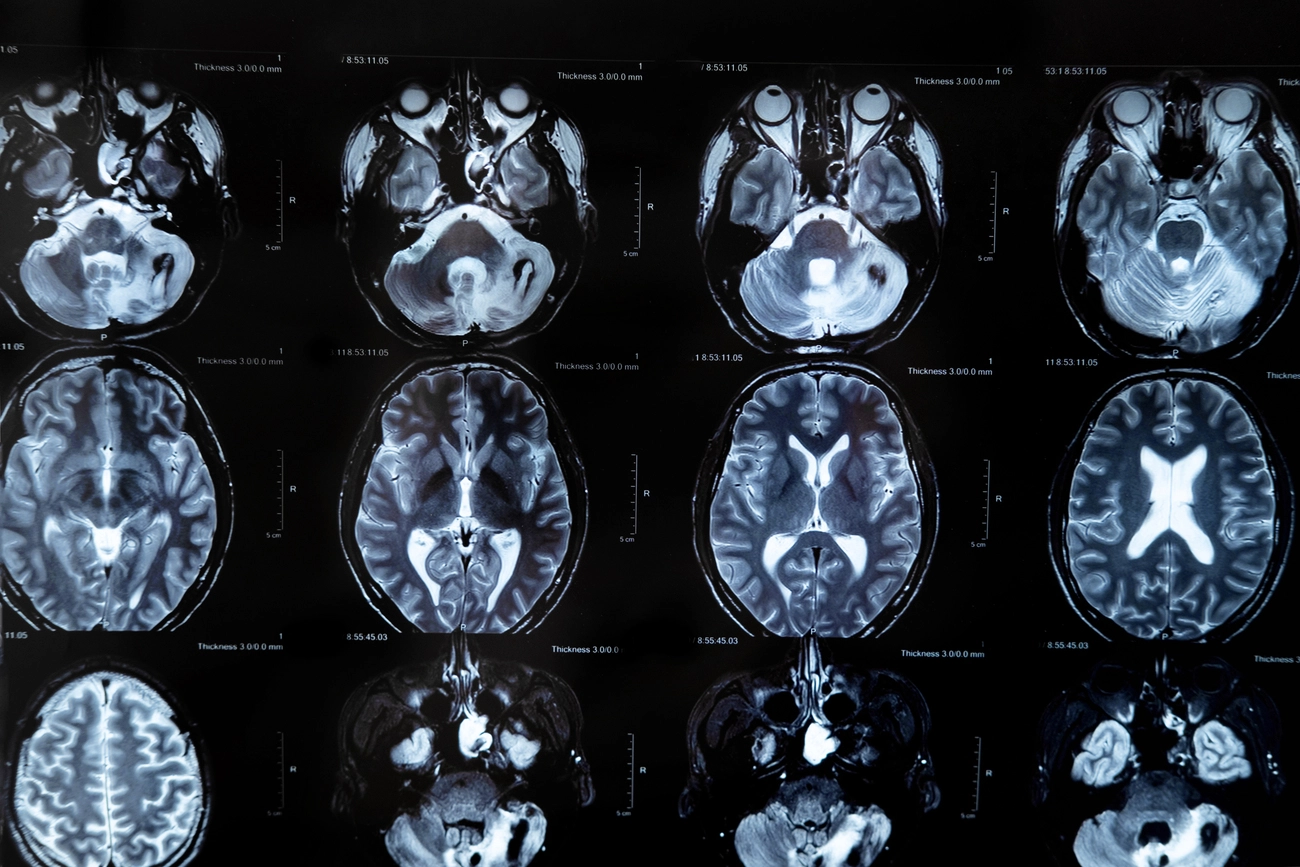

Utiliza campos magnéticos potentes y ondas de radio para generar imágenes detalladas sin necesidad de radiación. Esto hace que el procedimiento sea especialmente seguro y efectivo para detectar anomalías, desde pequeños tumores y hemorragias, hasta trastornos neurológicos complejos.

La resonancia de la cabeza funciona al colocar al paciente en una máquina de resonancia magnética (MRI, por sus siglas en inglés). Durante el estudio, el dispositivo crea un campo magnético que alinea temporalmente los protones en las células del cuerpo.

Luego, ondas de radio los estimulan para que produzcan señales, las cuales son capturadas y convertidas en imágenes detalladas del cerebro.